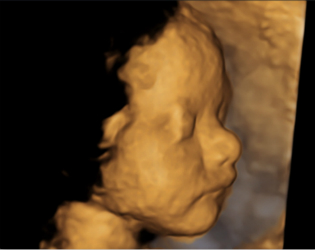

四维超声检查(动态三维超声检查)只是给宝宝拍了一张照片,对胎儿位置和姿势要求较高,胎儿孕周比较大才能拍的好,不能够评价胎儿的结构和发育情况。如果要求了解宝宝的结构是否正常,只需要选择系统产前超声检查。

点击这里看看四维彩超里的萌宝http://v.qq.com/page/u/8/9/u03089v9w89.html